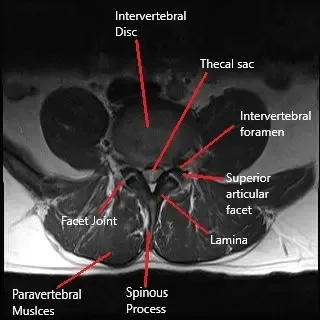

Se utiliza un estudio de imagen en forma de resonancia magnética para diagnosticar la re-hernia. Los estudios de resonancia magnética con gadolinio pueden utilizarse para diferenciar entre tejido cicatricial y re-hernia. Otros estudios de imagen, como una radiografía y un TAC, se utilizan más comúnmente para visualizar la anatomía ósea del paciente. La evaluación de la anatomía ósea ayuda a planificar una cirugía posterior si es necesario.